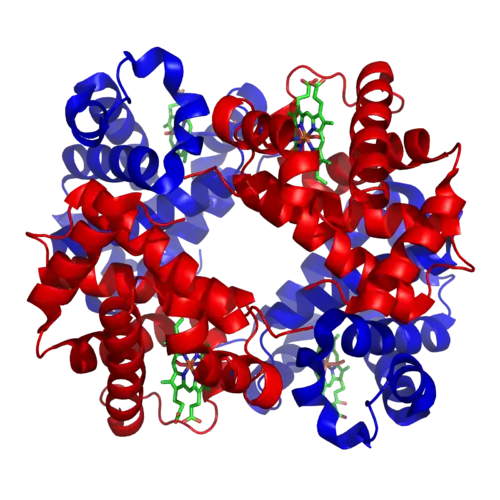

green = haem (or heme) groups

red & blue = protein subunits

Blood performs many important functions within the body, including:

- Supply of oxygen to tissues (bound to hemoglobin, which is carried in red cells)

- Supply of nutrients such as glucose, amino acids, and fatty acids (dissolved in the blood or bound to plasma proteins (e.g., blood lipids))

- Removal of waste such as carbon dioxide, urea, and lactic acid

- Immunological functions, including circulation of white blood cells, and detection of foreign material by antibodies

- Coagulation, the response to a broken blood vessel, the conversion of blood from a liquid to a semisolid gel to stop bleeding

- Messenger functions, including the transport of hormones and the signaling of tissue damage

- Regulation of core body temperature

- Hydraulic functions

Oxygen transport

About 98.5%[22] of the oxygen in a sample of arterial blood in a healthy human breathing air at sea-level pressure is chemically combined with the hemoglobin. About 1.5% is physically dissolved in the other blood liquids and not connected to hemoglobin. The hemoglobin molecule is the primary transporter of oxygen in mammals and many other species. Hemoglobin has an oxygen binding capacity between 1.36 and 1.40 ml O2 per gram hemoglobin,[23] which increases the total blood oxygen capacity seventyfold,[24] compared to if oxygen solely were carried by its solubility of 0.03 ml O2 per liter blood per mm Hg partial pressure of oxygen (about 100 mm Hg in arteries).[24]

With the exception of pulmonary and umbilical arteries and their corresponding veins, arteries carry oxygenated blood away from the heart and deliver it to the body via arterioles and capillaries, where the oxygen is consumed; afterwards, venules and veins carry deoxygenated blood back to the heart.

Under normal conditions in adult humans at rest, hemoglobin in blood leaving the lungs is about 98–99% saturated with oxygen, achieving an oxygen delivery between 950 and 1150 ml/min[25] to the body. In a healthy adult at rest, oxygen consumption is approximately 200–250 ml/min,[25] and deoxygenated blood returning to the lungs is still roughly 75%[26][27] (70 to 78%)[25] saturated. Increased oxygen consumption during sustained exercise reduces the oxygen saturation of venous blood, which can reach less than 15% in a trained athlete; although breathing rate and blood flow increase to compensate, oxygen saturation in arterial blood can drop to 95% or less under these conditions.[28] Oxygen saturation this low is considered dangerous in an individual at rest (for instance, during surgery under anesthesia). Sustained hypoxia (oxygenation less than 90%), is dangerous to health, and severe hypoxia (saturations less than 30%) may be rapidly fatal.[29]

A fetus, receiving oxygen via the placenta, is exposed to much lower oxygen pressures (about 21% of the level found in an adult's lungs), so fetuses produce another form of hemoglobin with a much higher affinity for oxygen (hemoglobin F) to function under these conditions.[30]